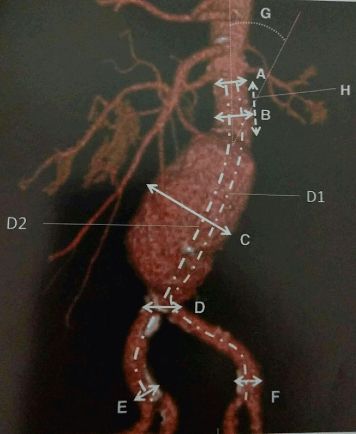

2. Abdominal aortic aneurysm (AAA) is defined as aortic diameter > 1.5 times that of the adjacent aorta. All sizes have to be measured in true axial sections (for an undulating aorta, true axial reconstructions have to be made from the coronal and sagittal reconstructions). Thus, for example, in the AAA below, measurements have to be taken on a 3D workstation by reconstructing in the true axial plane along A, B, C, D, E, and F as shown.

- Size –measure outer-to-outer diameter at proximal and distal landing zones, widest diameter of aneurysm from outer wall to outer wall, length of each landing zone, length of aneurysm and combined total length of aneurysm plus both landing zones

8. 15 mm of landing zone is traditionally required both proximally and distally to give proper attachment to the stent graft (see figure). A smaller distance may be manageable by newer techniques. A pajama graft (shaped like a pajama) is commonly used to achieve aneurysm occlusion, with the two limbs of the ‘pajama’ going into the two common iliac arteries.